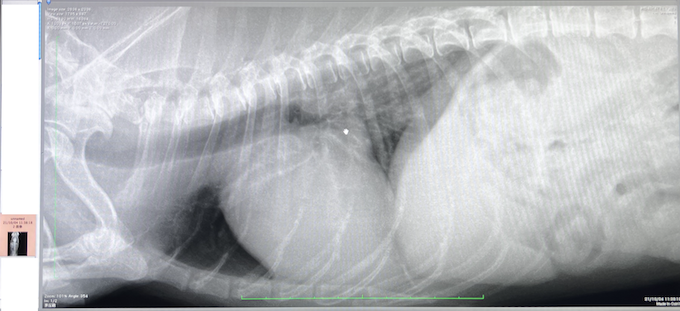

【2022年6月27日】

なんとかK先生の病院から退院。

そのまま2次病院へ移動し

7月7日手術を受ける運びとなりました。

※動物病院の先生に資料掲載許可を得ています

【2022年7月7日】

手術当日肺機能が低下し

大動脈酸素濃度が著しく下がっており

危険との判断で

一旦手術が延期されました。

現在入院を継続し

肺の状態を検査・治療してから

再度手術に挑みます。